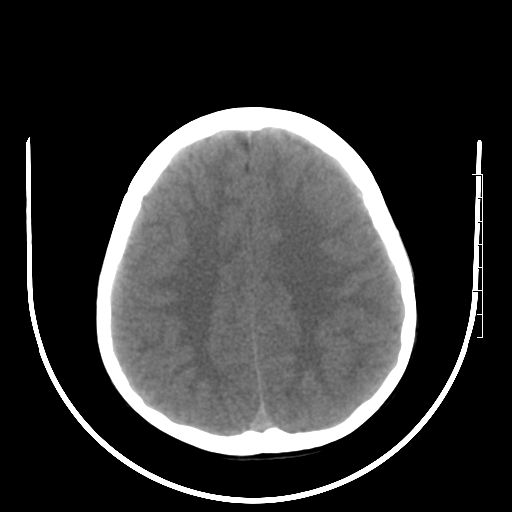

标题: PED3377:m、9y,恶心、呕吐,每月发作2-3次。 [打印本页]

标题: PED3377:m、9y,恶心、呕吐,每月发作2-3次。

颅脑ct轴位平扫颅内未见明确异常。

头颅ct平扫未见异常

颅脑ct平扫未见异常。